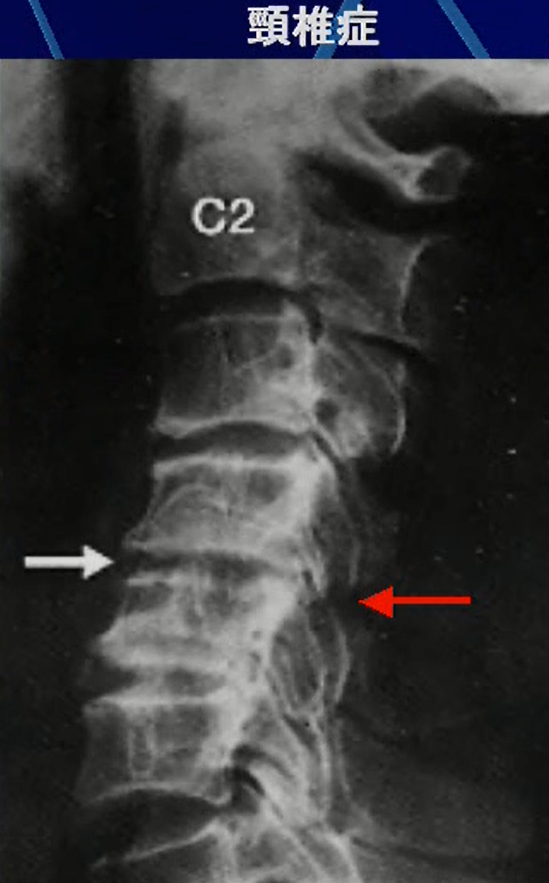

●後縦靭帯骨化の合併

右のレントゲンを見て違和感は感じますでしょうか。

本来、椎骨と椎骨の間は黒く映るのですが上の方の椎骨間に白いものが映っています。

これが後縦靭帯が骨化している状態ですが頚椎症と合併してしまうと症状が悪化するので注意が必要です。